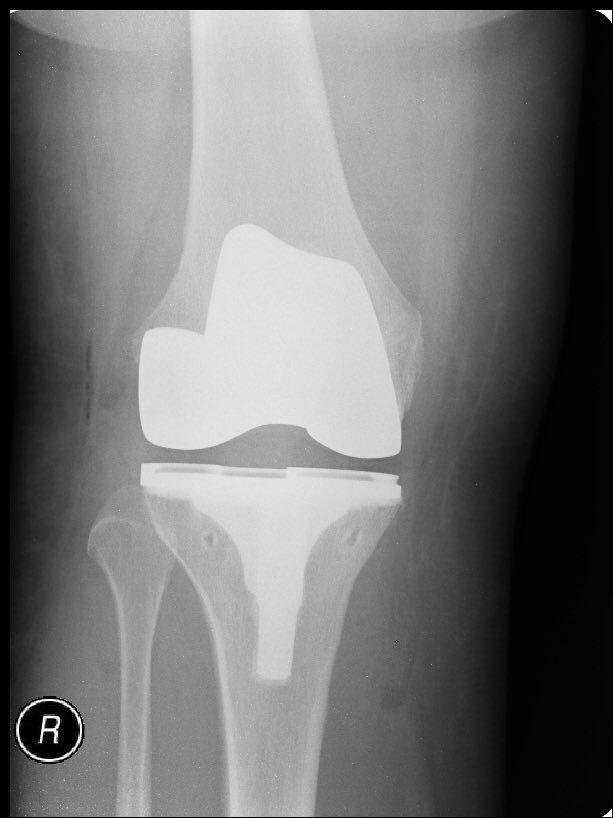

استخدام صفة او نوع معين في المفصل الصناعي hyperflexsion (مايسموه مفصل إسلامي) أي إعطاء مدى ثني أكثر لا يعني بالضرورة الجلوس والثني على الركبة كما في وضعية جلوس التشهد

فقاعدة اساسية لدينا في #جراحة المفاصل الصناعية..... مدى حركة المفصل تعتمد بشكل الكبير على وضعها قبل العملية

لكن هناك العديد من الطرق خلال العملية او التقنيات التي تساعد على زيادة مدى حركة المفصل بشرط الحفاظ على ثبات ودعم المفصل

أيضا في بداية مراحل #الخشونة ننصح المريض بتجنب الجلوس والتربيع على الأرض، إضافة إلى استخدام الكرسي للصلاة

لتجنب تسارع عملية الاحتكاك والخشونة بسبب الضغط الكبير عليها

ففي المفاصل الصناعية ننصح المريض بالاستمرار بتجنب هذه الوضعيات ايضاً